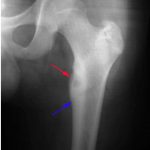

U xương dạng xương (Osteoid osteoma) là một tổn thương xương lành tính. Đó là một ổ nhỏ (nidus) bao quanh là vùng xơ cứng phản ứng có kích thước rất nhỏ khoảng từ 1,5-2cm, xuất hiện chủ yếu tại các thân xương dài của chi dưới (80-90%).Chiếm 10% tất cả các khối u xương lành tính và chiếm 5% trong tổng số các loại u xương nguyên phát….